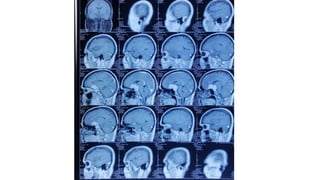

Radiological findings

• Multiplaner sagital ,coronal and axial images show a well defined ,midline, broad dural based,

Radiological findings • Multiplanersagital ,coronal and axial images show a well defined ,midline, broad dural based, lobulated T1WI iso , T2WI iso to slightly hyper and FlAIR hyperintense mass noted in suprasellar area having extension forwards along the planum sphenoidale and backwards along the dorsum sellae. • After IV contrast avidly homogenous enhancement of the lesion and adjacent linear dural enhancement over the clivus and planum sphenoidale representing dural tail are noted. • The lesion causing compression over the optic chiasma, pituitary gland and floor of 3rd ventricle, and encasing the supraclinoid ICA, ACA and MCA of both sides. • The mass effect is evidenced by obliteration of Suprasellar & interpeduncular cysterns and symmetrical indentation of underlying cerebral cortex. • No perilsional edema is noted • However lateral , 3rd and 4rth ventricles appear normal • Complementary CT cut was taken and showing iso to slightly hyperdense lesion. No calcification is noted. Bone CT shows bony hyperostosis at planum sphenoidale .Sellar size is within normal limit

Radiological diagnosis • Suprasellarmeningioma with planum sphenonale and dorsum sallar extension